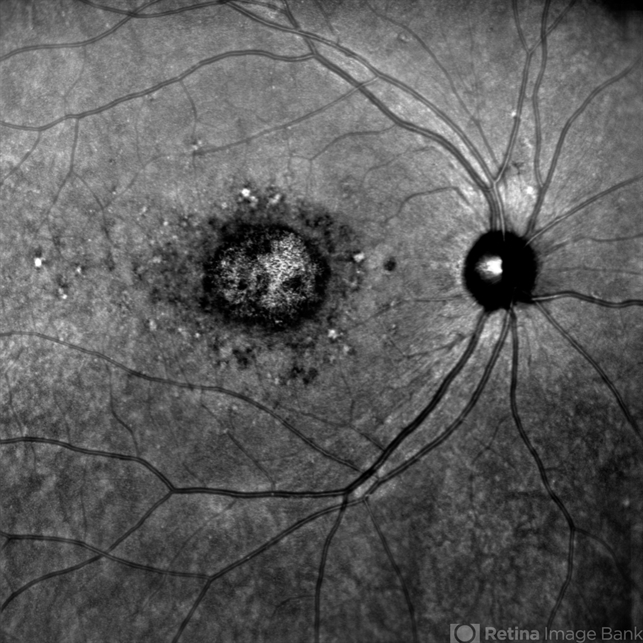

- Stargardt disease, infrared image

- Dr Malvika Singh, Retina Foundation, Ahmedabad, India

Scanning laser ophthalmoscope

Mirante SLO/OCT - Description

- Infrared fundus photograph of a 22 year old female with Stargardt's disease.